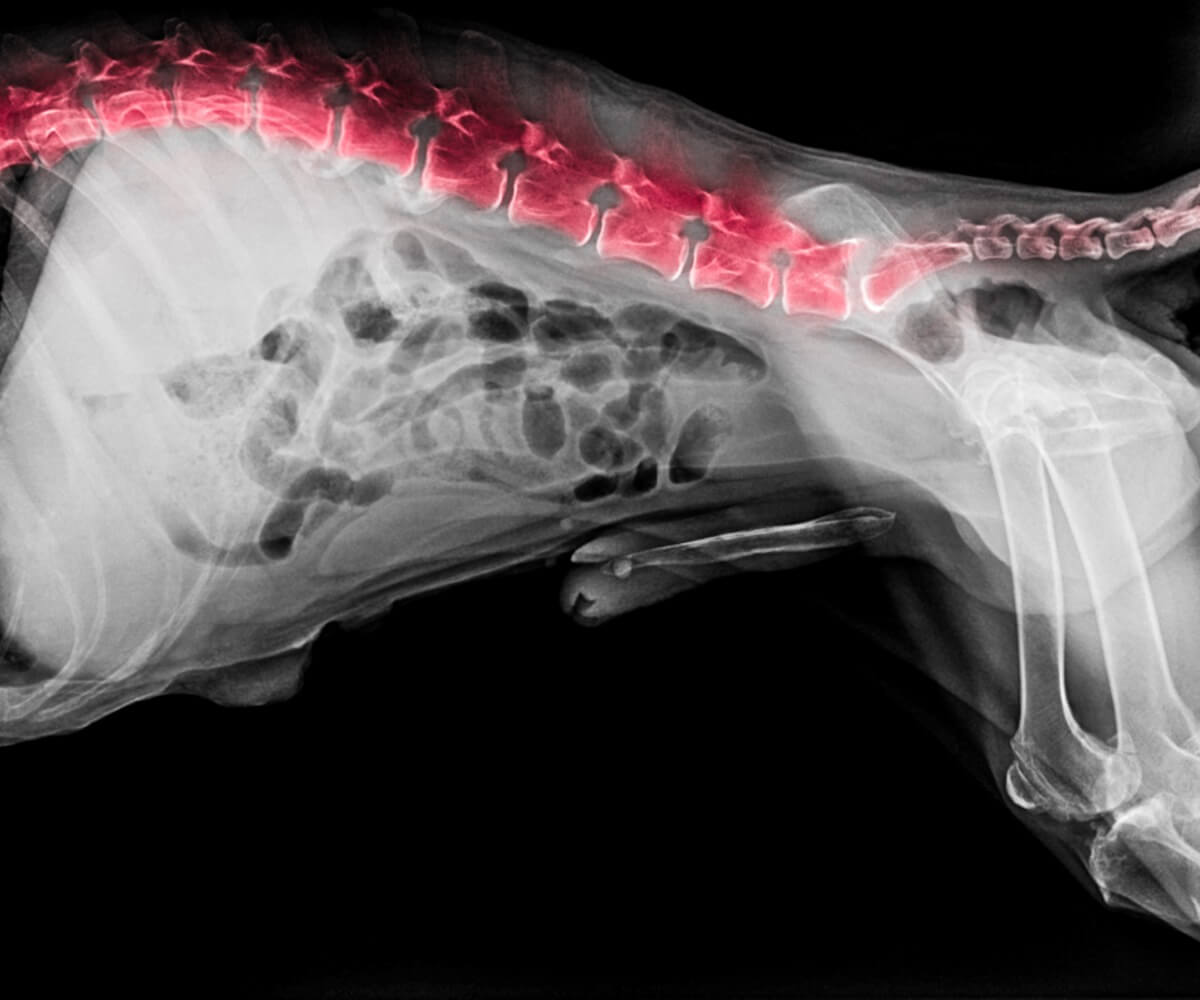

9. Síndrome de Wobbler en perros san bernardo

Esta es otra de las enfermedades frecuentes en el san bernardo. Se trata de una dolencia cuyo origen está en el área cervical. Concretamente, es un problema de las vértebras cervicales y discos intervertebrales, que provoca la compresión de la médula espinal. Esto deriva en problemas de tipo neurológico.

De hecho, su nombre (Wobbler), se emplea para definir el caminar tambaleante que aparece en el perro cuando sufre este síndrome, puesto que wobble es “tambalearse” en inglés. Además del tambaleo, otros síntomas de esta enfermedad son rigidez en el cuello, cansancio, debilidad, hinchazón de las extremidades, parálisis parcial o completa o dificultad para levantarse y moverse.